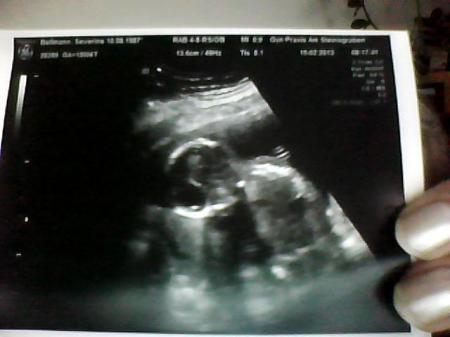

hoffe man kann gut was sehen